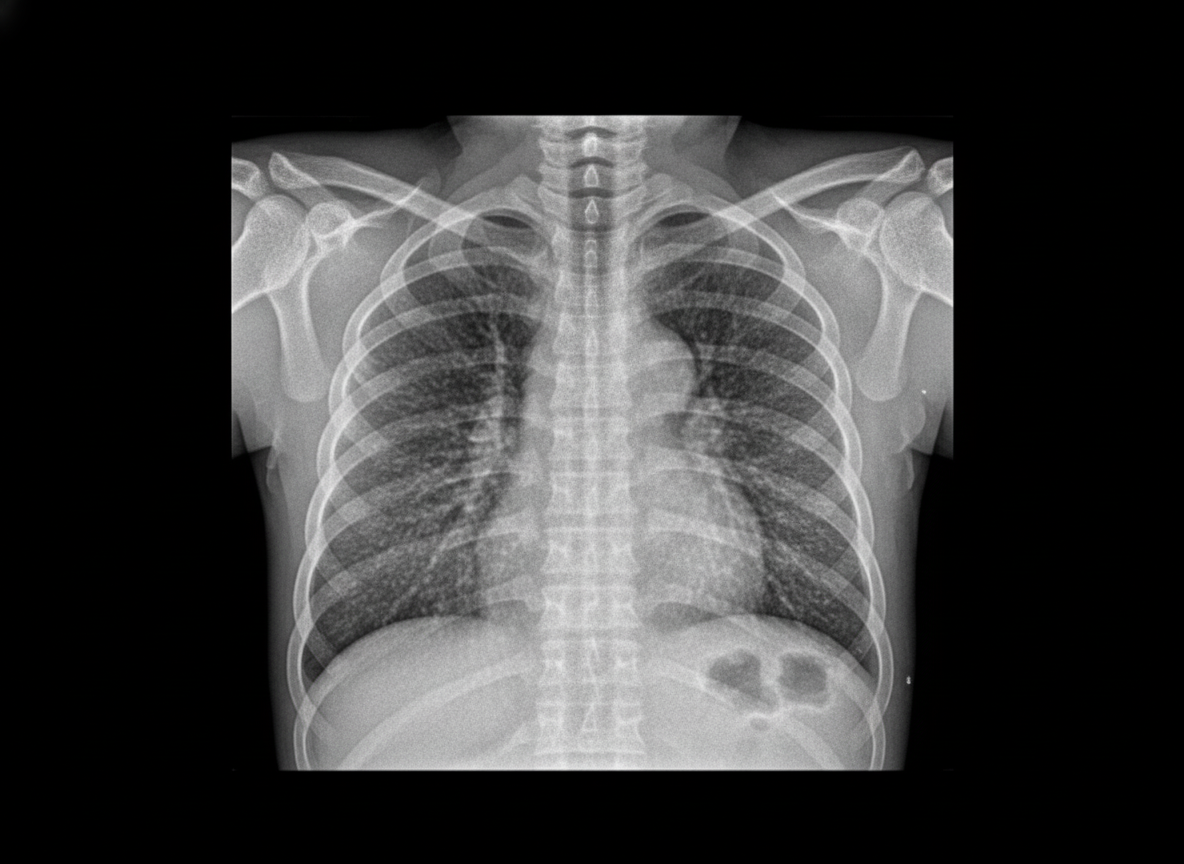

An 8-hour-old term infant develops increased respiratory distress, hypothermia, and hypotension. A complete blood count (CBC) demonstrates a white blood cell (WBC) count of 2500/mL with 80% bands. The chest radiograph is shown below. Which of the following is the most likely diagnosis?

Explanation: ***Group B streptococcal pneumonia*** - **Leukopenia** (WBC 2500/mL) with **80% bands** in a term neonate within the first 24 hours is the hallmark of **early-onset GBS sepsis/pneumonia**. - Clinical presentation of **respiratory distress**, **hypothermia**, and **hypotension** with bilateral granular infiltrates on chest X-ray mimicking **RDS** in a term infant strongly suggests GBS pneumonia. *Congenital syphilis* - Typically presents with **hepatosplenomegaly**, **skin rashes**, and **osteochondritis**, not acute respiratory distress in the immediate newborn period. - **Normal WBC count** or lymphocytosis is more common, not severe leukopenia with left shift. *Diaphragmatic hernia* - Chest X-ray would show **bowel loops in the thoracic cavity** and **mediastinal shift**, not bilateral granular infiltrates. - **WBC count** would typically be normal unless secondary complications develop. *Transient tachypnea of the newborn* - Occurs in **term infants** born via **cesarean section** with **streaky perihilar markings** on chest X-ray, not bilateral granular infiltrates. - **Normal WBC count** and absence of systemic signs like hypothermia and hypotension distinguish it from sepsis.